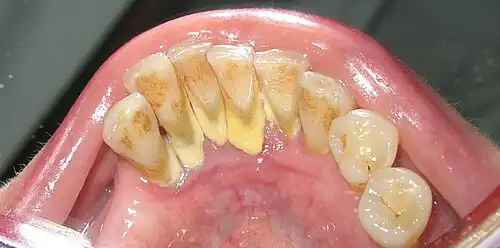

Heavy staining and calculus deposits exhibited on the lingual surface of the mandibular anterior teeth, along the gumline

Supragingival calculus formation is most abundant on the buccal (cheek) surfaces of the maxillary (upper jaw) molars and on the lingual (tongue) surfaces of the mandibular (lower jaw) incisors.[18] These areas experience high salivary flow because of their proximity to the parotid and sublingual salivary glands.